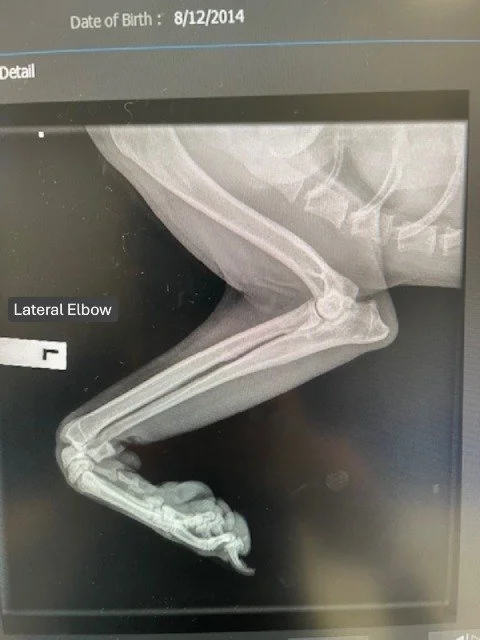

ELBOW DYSPLASIA

Elbow dysplasia is an umbrella term for developmental conditions affecting the elbow joint, commonly seen in large-breed dogs. It leads to pain, lameness, and arthritis, often presenting as intermittent lameness in young dogs, while in older patients, progressive joint disease results in chronic stiffness and discomfort.

The condition may involve fragmented coronoid process (FCP), osteochondritis dissecans (OCD), ununited anconeal process (UAP), or elbow incongruity. Surgical options may be considered depending on age and suitability, but many cases are not surgical candidates, making long-term management the primary approach.